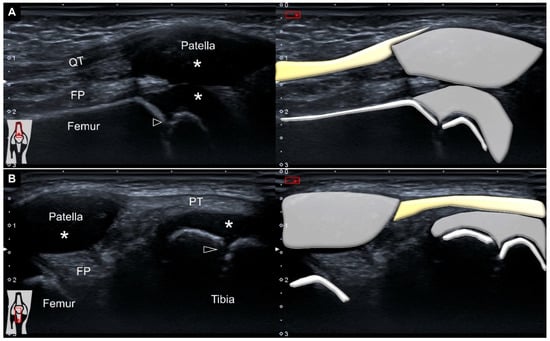

With his right knee extended in the supine position, ultrasound imaging over the suprapatellar region demonstrated no effusion, an intact quadriceps tendon, a non-ossified patella, prominent femoral cartilage, and a clear epiphyseal growth plate (Figure 1A). The transducer was relocated distally to scan the infrapatellar area. Likewise, the fibrillar appearance of the patellar tendon remained without any remarkable pathologies (Figure 1B).

Figure 1. Ultrasound imaging and schematic drawing of the (A) suprapatellar and (B) infrapatellar regions. QT: quadriceps tendon; FP: fat pad; PT: patellar tendon; *: hyaline cartilage; black arrowheads: growth plate.